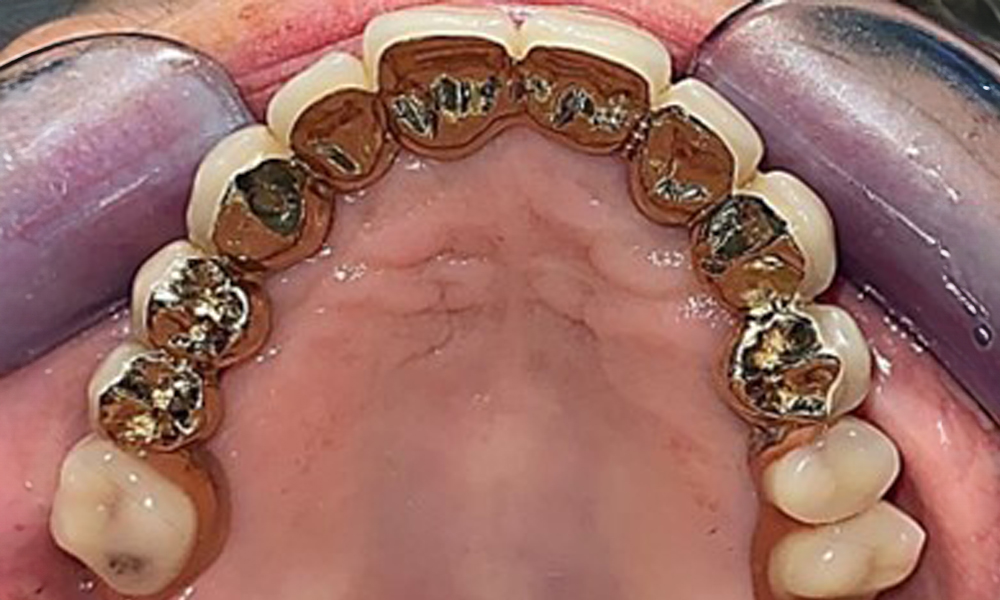

The patient was fitted with a combined removable maxillary telescopic prosthesis more than 25 years ago (Fig. 1, Fig. 2, Fig. 3) and is very happy with her dentures. The patient has an adequate fixed denture for the mandible (Fig. 4).

Occlusal view: Maxilla with removable, palateless denture.

Fig. 3: Occlusal view: Maxilla with removable, palateless denture.

The dental findings are as follows: Combined removable implant and tooth-supported telescopic prostheses on implants 15, 13, 21, 23, 24, 25 and tooth 11 (Fig. 1, Fig. 2, Fig. 3). The patient was fitted with a fixed mandibular denture. Adequate bridges were present over 37 to 34 and 45 to 47 (Fig. 4), the crown margins were intact and there were no active caries. A composite filling with a marginal gap was present on tooth 43. There was mandibular gingival recession, exposing 1 to 3 mm of root surface. This also applies to 11.